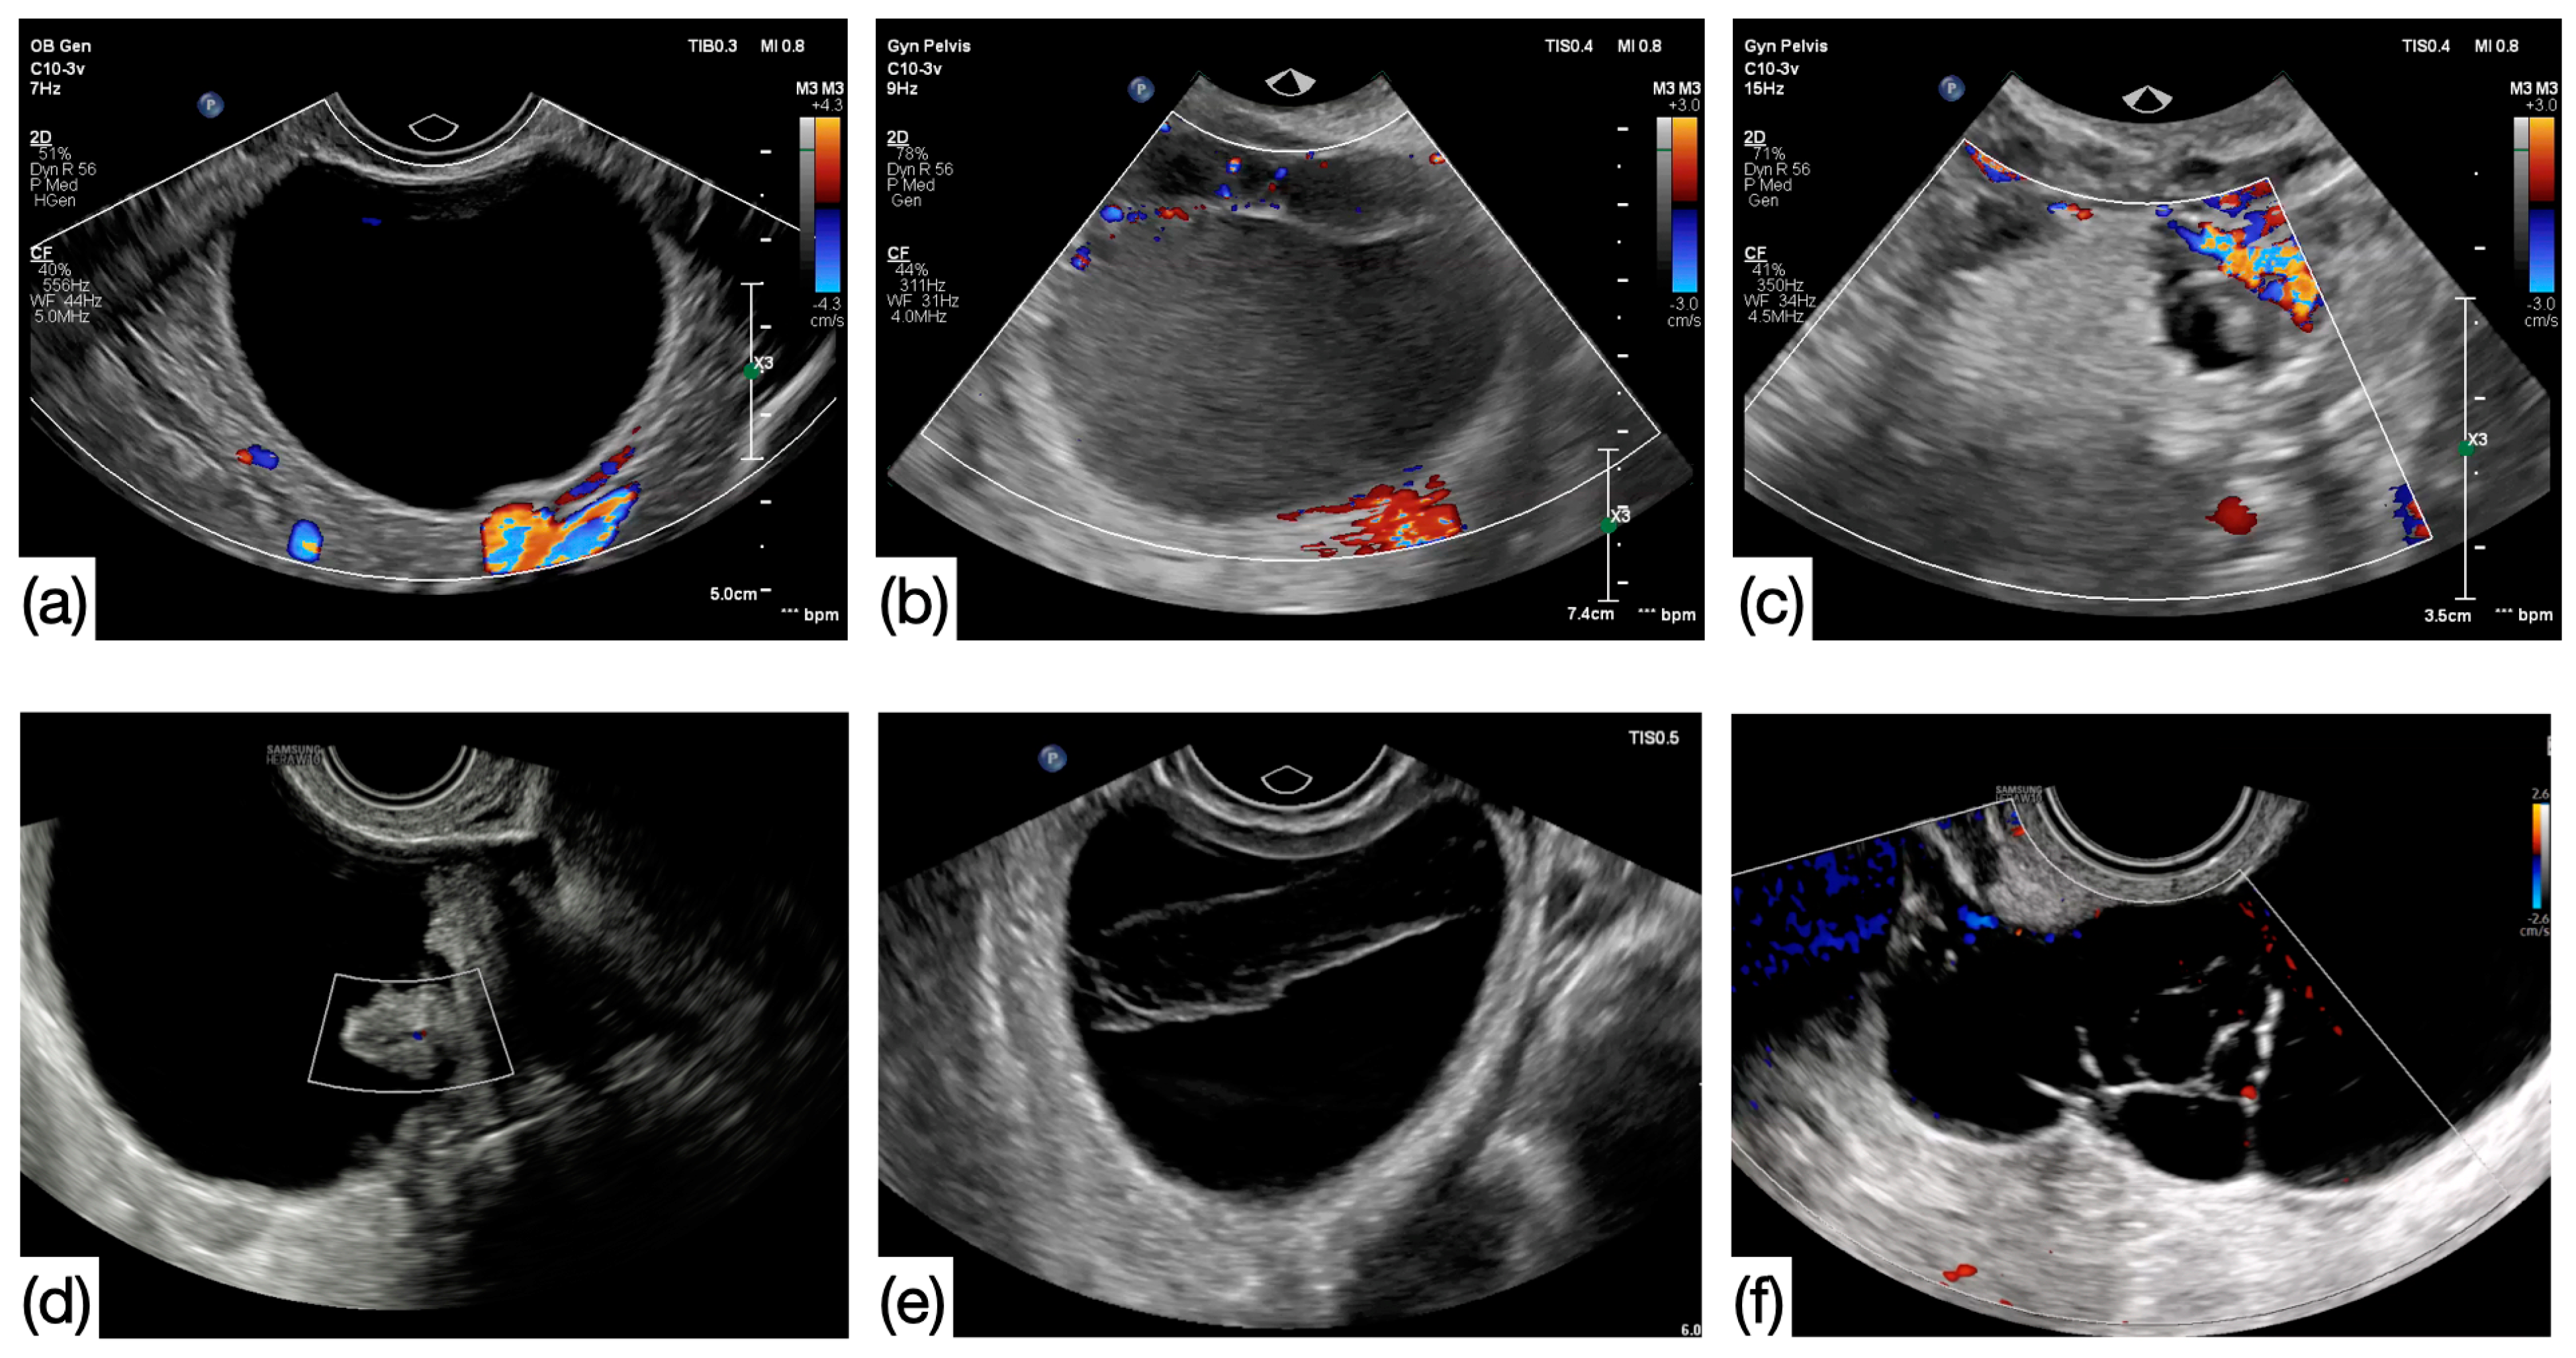

This study was performed in the Department of Obstetrics and Gynecology at the University of Debrecen, Debrecen, Hungary. The imaging properties of peri- (PEM) and postmenopausal (POM) ovarian cysts were examined preoperatively. All patients underwent transvaginal ultrasound examinations preoperatively (ATL HDI-3000, Bothell, DC, USA, equipped with 5.9 MHz transvaginal probe and Medison Accuvix XQ, Medison Co., Ltd., Seoul, Republic of Korea, equipped with a 5–8 MHz transvaginal probe Kretztechnik AG, Zipf, Austria). Patients over the age of 40 with cystic adnexal masses were consecutively recruited. Patients without clinical signs of menopause or climacteric symptoms were categorized into the PEM group, as well as those who previously underwent hysterectomy under the age of 50 (range: 40–54 years, average: 45.57 years). A lack of regular periods for more than one year or hysterectomy in patients over 50 years of age were selected for the POM group (range: 41–88 years, average: 61.24 years). Overall, 343 patients with 379 cystic structures were involved in the study. US examinations were performed independent of the menstrual cycle and were repeated within three months in 168 cases (44.32%). When follow-up was performed, only the preoperative US finding was chosen for inclusion. According to the US findings, the following two groups were formed: (1) simple cysts: unilocular, anechoic cysts without any solid structure and (2) complex cysts: cystic structures with different parameters and even containing solid parts. Examples shown in Figure 1. Imaging characteristics and size were matched with histology and CA125 levels. The cut-off level for CA-125 was 35 kIU/L. According to the size of the cysts, two subgroups were formed within each reproductive group, and 5 cm was chosen for this purpose. Risk factors affecting the formation of cystic structures in the ovary were also observed in this study, such as parity, previous pelvic surgeries, and family history of ovarian cancer.

Figure 1.

Ultrasound images of simple (a) and complex cysts (b–f). (a) Simple cyst: unilocular, anechoic, smooth, and regular-walled cyst without any solid component (b) ground glass content—endometrioma, (c) mixed echogenicity content—dermoid, (d) solid papillary projection, (e) hemorrhagic content, and (f) multilocular cyst (images of B.E.).